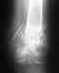

Удалили винты 3 штуки из бедра.

Полтора года назад ставили т.к. был перелом шейки.Когда можно полностью наступать на ногу и через сколько идти на работу. Особо нога не болит.